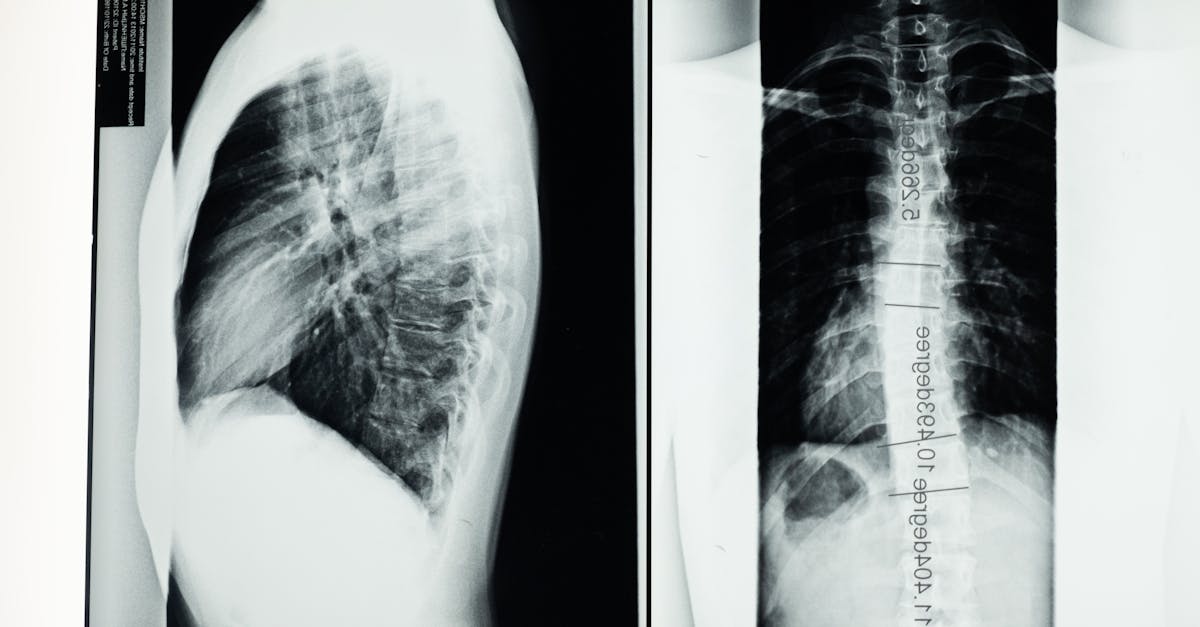

La décompression neurovertébrale utilise un appareil spécialisé pour exercer une traction contrôlée sur la colonne vertébrale. Cela crée un espace entre les vertèbres, réduisant ainsi la pression sur les nerfs et favorisant la circulation sanguine. Ce processus permet aux disques intervertébraux de se réhydrater et de se repositionner, ce qui est essentiel après une chirurgie.

La décompression neurovertébrale utilise des dispositifs spécialisés qui applient une traction contrôlée sur la colonne vertébrale. Cette technique crée un espace entre les vertèbres et permet aux disques intervertébraux de se réhydrater et de se repositionner, réduisant ainsi la pression sur les nerfs adjacents. Lorsque cette pression diminue, les symptômes associés à la douleur et à l’inflammation s’estompent, améliorant ainsi la mobilité et la posture du patient.

Dans le cadre de cette thérapie, des appareils spécialisés, souvent utilisés sur une table de traction, exercent une pression contrôlée sur la colonne vertébrale, permettant de réduire la tension sur les disques intervertébraux. Cette approche peut s’intégrer efficacement dans le parcours de soins post-opératoires, offrant un soutien nécessaire pour restaurer une posture correcte et améliorer la fonction musculaire. Grâce à des séances planifiées et à une évaluation régulière des progrès, les thérapeutes peuvent ajuster les traitements pour s’adapter aux besoins spécifiques de chaque patient.